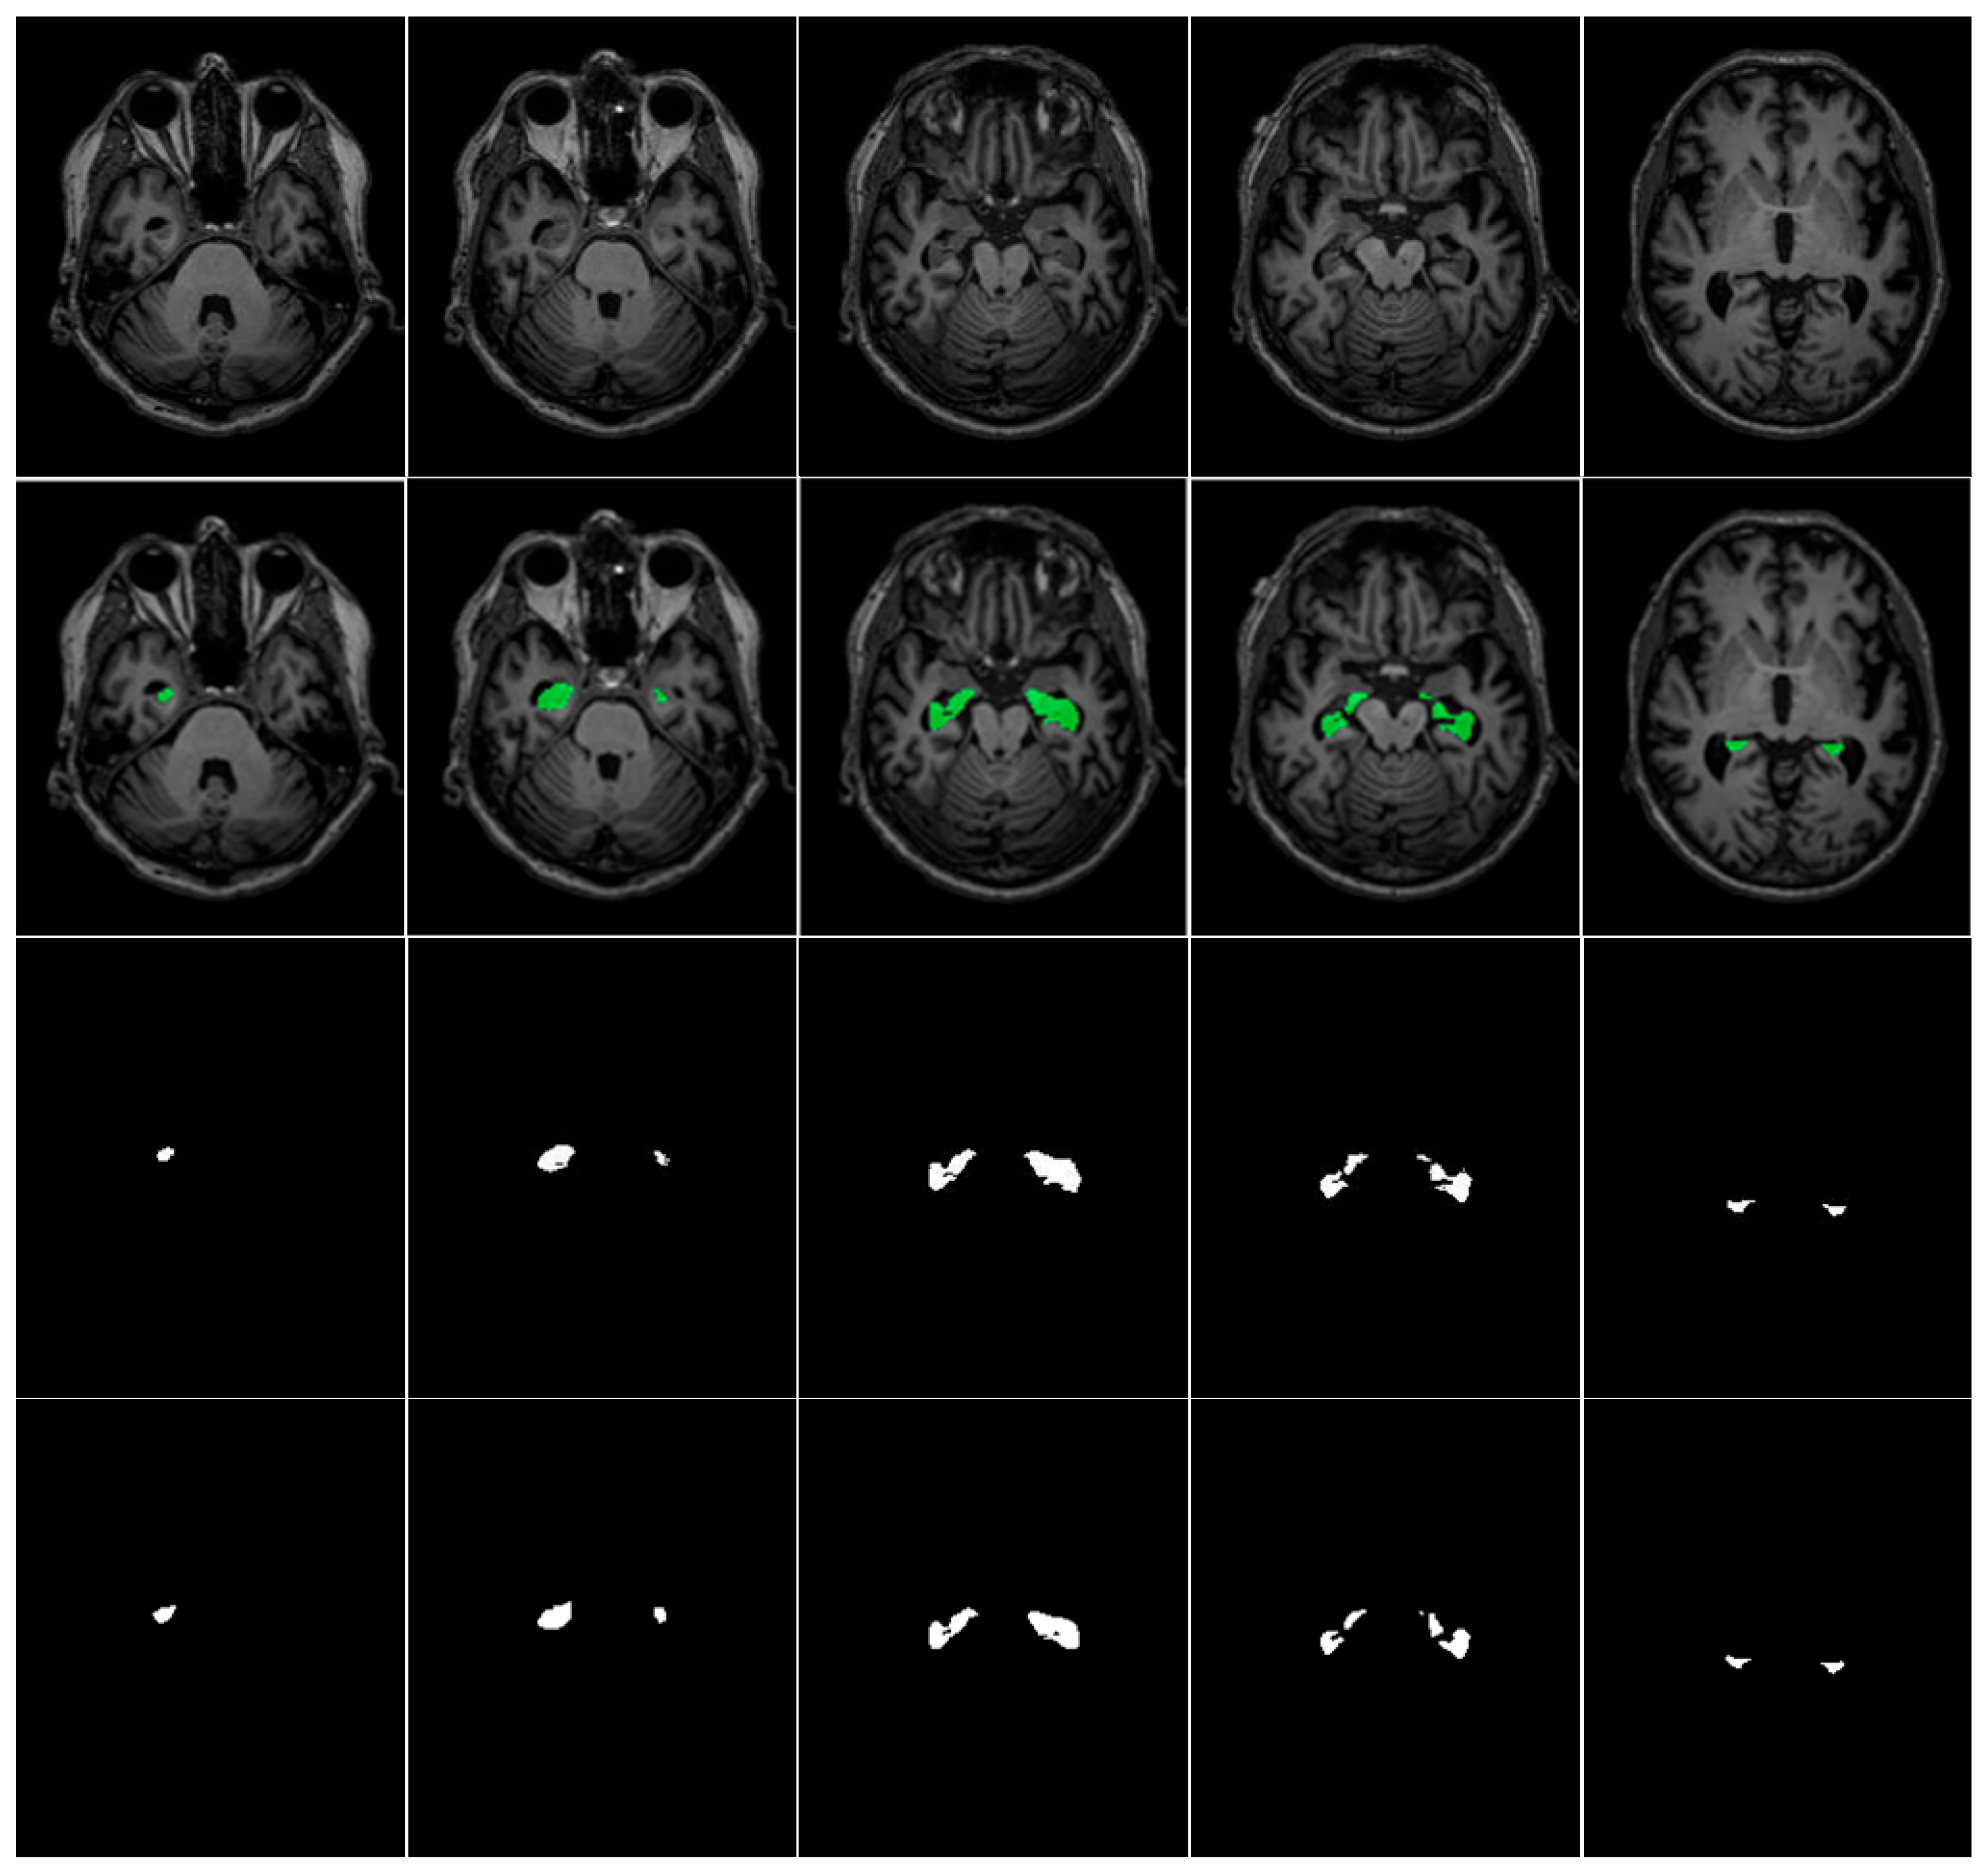

This indicates that CSDA-UNet, by incorporating multiple spatial attention modules and inter-slice attention modules, can better enhance the model’s ability to extract spatial features, thereby improving segmentation performance and stability. The slightly lower recall of CSDA-UNet arises from its focus on reducing false positives via channel–spatial dual attention, which improves precision but may miss some boundary regions, especially given the small size of hippocampal areas relative to the background. An illustration of the segmented regions after model training is shown in Figure 10 for the ADNI dataset and Figure 11 for the Decathlon dataset, demonstrating a high capability for hippocampal segmentation. CSDA-UNet showed only a slight increase in inference time over U-Net, U-Net + SA, and U-Net + ISA, while maintaining similar batch throughput. This minor cost is justified by its significant accuracy and precision gains, confirming its clinical practicality.

Figure 10. MRI images (1st row), masks overlays (2nd row), ground truth (3rd row), and CSDA U-Net model segmented regions (4th row) for ADNI Dataset.

Figure 11. MRI images (1st row), masks overlays (2nd row), ground truth (3rd row), and CSDA U-Net model segmented regions (4th row) for Decathlon Dataset.